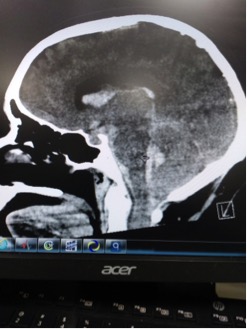

Patient was rushed to CT given clinical hx and presentation.

CT read as large amount of subarachnoid hemorrhage, suspicious for ruptured aneurysm.